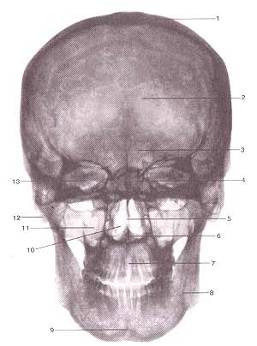

Вид спереди.

1-крыша (свод) черепа;

2-лобная кость;

3-лобная пазуха;

4-ячейки решетчатой кости;

5-костная перегородка полости носа;

6-передняя носовая ость;

7-межверхнечелюстной шов;

8-нижняя челюсть;

9-подбородочный выступ;

10-полость носа;

11-верхнечелюстная пазуха;

12-сосцевидный отросток;

13-глазница.